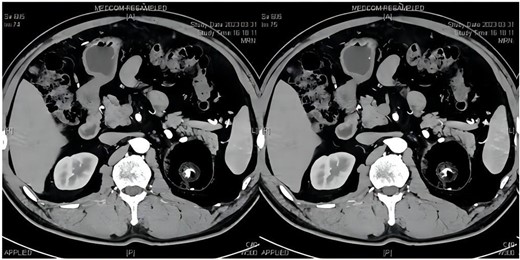

The patient was a 52-year-old male with a tumor in the left adrenal gland, measuring 7.2*7.5 cm, who had normal blood pressure and was in good health. He was admitted to the hospital for adrenal hormone examination, which showed normal adrenal function (renin: 2.34 pg/mL, aldosterone: 74.11 pg/mL, Adrenocorticotropic hormone: 35.20 pg/mL, cortisol: 243.0 nmol/L). Enhanced computed tomography (CT) of adrenal gland showed left adrenal region with rounded mixed density foci, with smooth margins, internal mature fat as the main focus, local mixed flaky slightly high density foci, and an internal “sac within a sac”, with a maximal cross-section of ~7.4*7.3 cm, with insignificant enhancement (Fig. 1), which was consistent with the manifestation of teratoma. The patient underwent laparoscopic adrenal tumor resection under general anesthesia, during the operation, the tumor was found to be closely adherent to the surrounding tissues, and the tumor was removed completely by blunt dissection with a peeling rod, and the patient’s vital signs were stable during the operation, and the tumor was incised under the table, which showed cystic solidity, with yellowish-white turbid contents, and hairy tissues were seen in the interior (Fig. 2A). Pathologic diagnosis was adrenal mature cystic teratoma (Fig. 2B) and the patient recovered well without any complications.

Adrenal gland CT: left adrenal gland huge tumor, size ~7.2*7.5 cm, internal fat mainly, see a “sac within a sac”, see calcification foci inside.